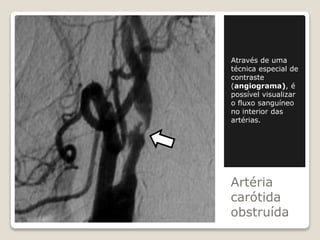

Através de uma

técnica especial de

contraste

(angiograma), é

possível visualizar

o fluxo sanguíneo

no interior das

artérias.

Artéria

carótida

obstruída

Artéria carótida obstruída Através de uma técnicaespecial de contraste (angiograma), é possível visualizar o fluxo sanguíneo no interior das artérias.

• #8 Nesta técnica é inserido um catéter na virilha ou no braço do paciente (consoante o local a observar) que é empurrado até chegar aos vasos a observar. O catéter serve para transportar e libertar no local uma tintura de contraste que permite observar os vasos sanguíneos quando se faz uma radiografia posterior. Pode no entanto induzir problemas secundários se o doente for alérgico ao meio de contraste, ou eventualmente provocar problemas cardíacos se passar por artérias já obstruídas.